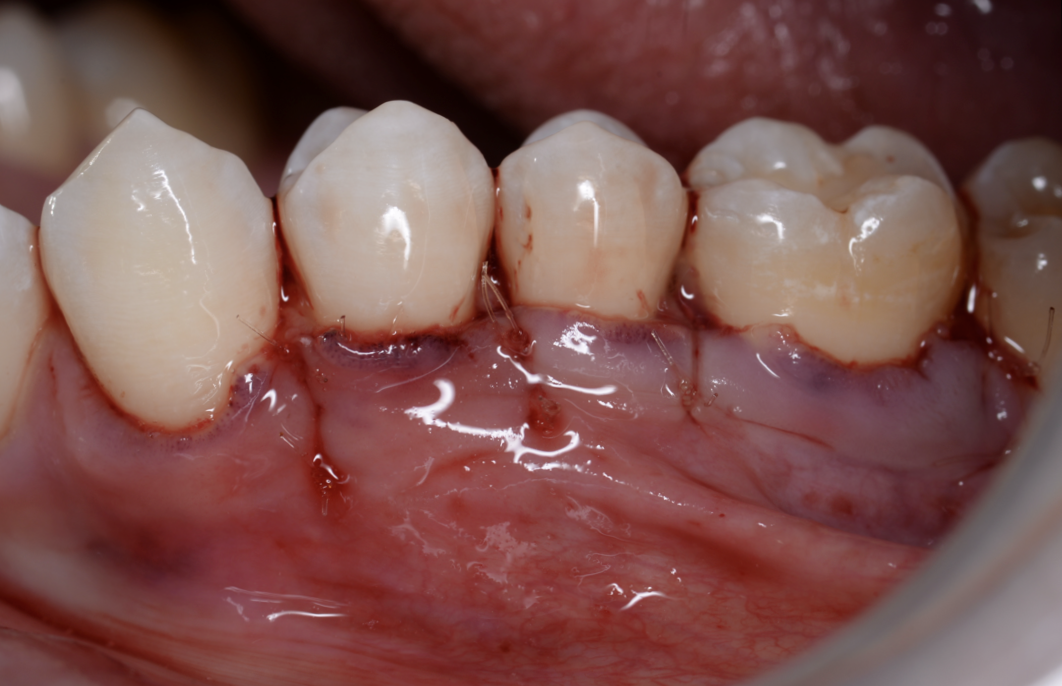

【池袋|歯肉退縮の治療】結合組織移植術によるル...